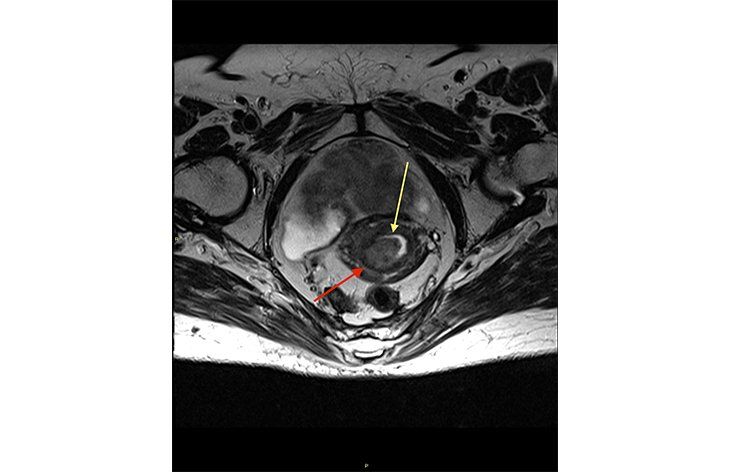

Researchers analyzed recurrence and survival outcomes for clear cell ovarian carcinoma in the JGOG3017/GCIG trial.